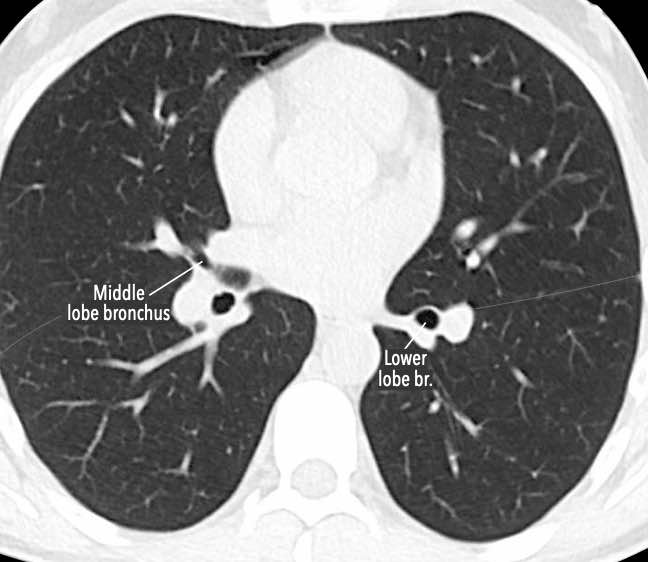

Phế quản trên CT

Cuộn qua các hình ảnh để quan sát khí quản phân chia thành phế quản chính phải và trái, sau đó tiếp tục phân chia thành các phế quản thùy và phế quản phân thùy.